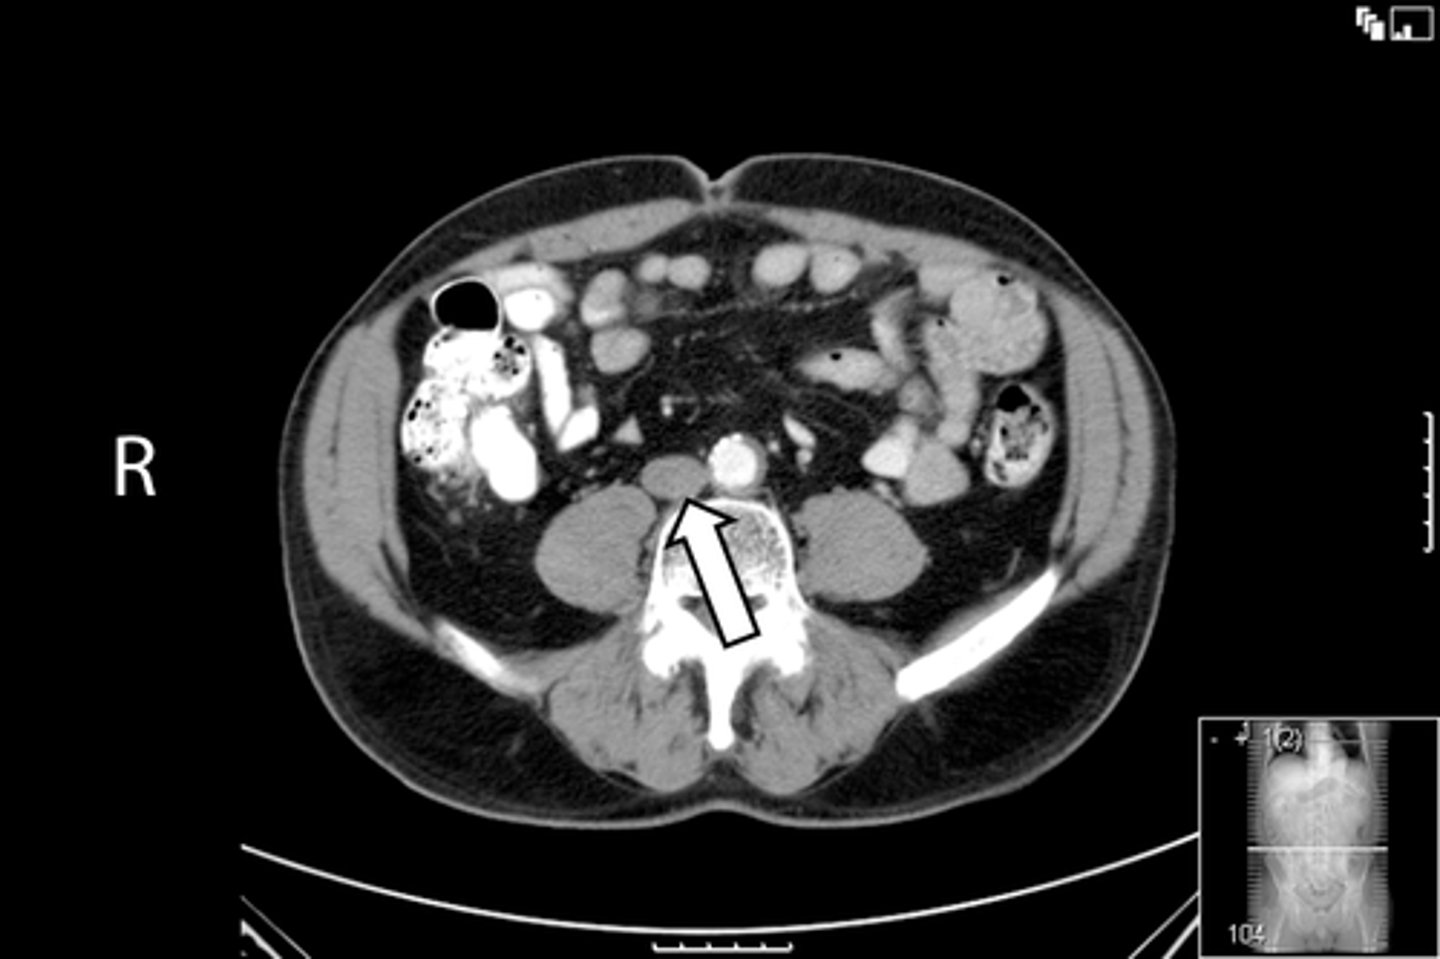

<p>What is indicated in the image?</p>

Axial male pelvis CT

What is the image?

<p>What is the image?</p>

65

New cards

Descending colon

What is indicated in the image?

66

L common iliac artery

67

L gluteus muscle

68

L iliacus muscle

69

L ilium

70

L psoas muscle

71

R common iliac artery

72

R gluteus muscle

73

R iliacus muscle

74

R ilium

75

R psoas muscle

76

R and L rectus abdominis